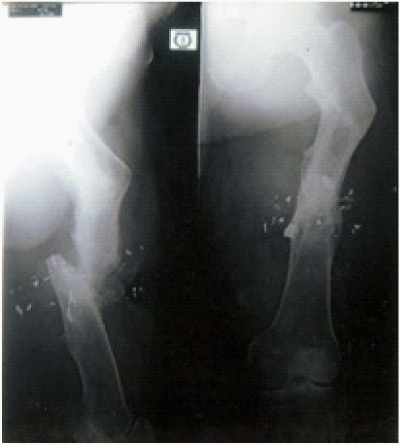

Figure 6 No more LLD (Limb length discrepancy). Ilizarov in situ after 8 months follow up.

Figure 7 After removal of Ilizarov fixator 10 months follow up. Lengthening of tibia and fibula is visible.